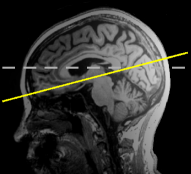

As AD advances, several brain regions develop structural deformation and atrophy [3]. Structural Magnetic Resonance Imaging (sMRI) is one of the most widely employed neuroimaging tools for predicting this disorder through identifying brain atrophy [4] (see Fig. 1). In addition to sMRI (referred to as MRI in this paper), non-invasive biomarkers such as (1) demographic information (e.g., age and education) [5], and (2) cognitive test scores [4] can also be used to provide possible discriminative information for diagnosing AD in the early stages. Several studies [4, 6, 7, 8, 9] have addressed the MCI-to-AD conversion issue using neuroimaging methods in conjunction with the biomarkers.

Figure 1: MRI samples of (a) Cognitively Normal (CN) and (b) AD classes from Alzheimer’s Disease Neuroimaging Initiative database (ADNI-1) [10]. In order to demonstrate the subtle brain atrophy, we highlighted the affected regions.